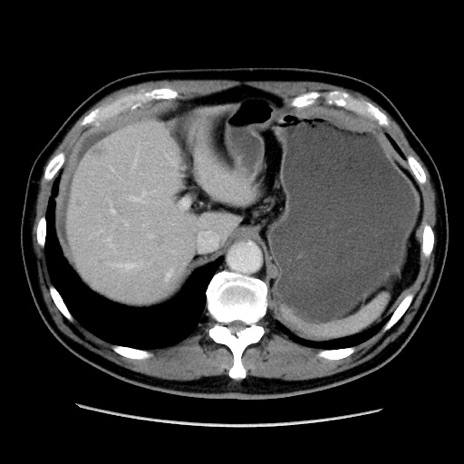

症例16(横断像)

【症例】 70歳代男性

【主訴】 腹痛、嘔吐

【現病歴】 約1ヶ月前より間欠的に腹痛と嘔吐あり、当院消化器内科を受診したところCTで多発する肝臓のLDAを指摘され、精査中であった。以降は消化器症状は安定していたが、2日前より嘔気と腹痛があり、同日より排便・排ガスが消失した。改善認めず、 本日、救急外来を受診した。

【既往歴】 大腸ポリープ切除後。

【身体所見】意識清明・会話良好、BT 36.3℃、BP 127/80mmHg、 P 80bpm、腹部:膨満あり、平坦・軟、上腹部正中および下腹部正中に圧痛あり、反跳痛なし、筋性防御なし。

【データ】WBC 7200、CRP 0.77